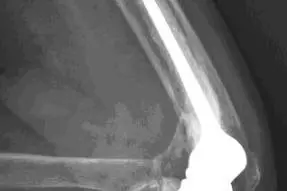

Figur 2 viser røntgenbilder av en hofte med artrose (figur 2a til venstre) og en hofte som har fått en sementert hofteprotese (figur 2b til høyre).

I prinsippet består en hofteprotese av en stamme som går ned i lårbenet, et hode som settes på toppen av stammen som erstatning for lårbenshodet, og en kunstig hofteskål (koppen) (figur 1). Forskjellige stammer kan kombineres med kopper av forskjellige merker, slik at kombinasjonsmulighetene blir svært mange.

Det er to hovedprinsipper for innfesting av protesedelene mot pasientens bein; enten med beinsement (polymetylmetakrylat) eller uten sement. Det er flere produsenter som lager beinsement. På begynnelsen av 1990-tallet ble Boneloc bensement brukt i Norge. Denne og to andre sementtyper viste seg å gi dårlige resultater, og disse sementtypene gikk ut av bruk for flere år siden.